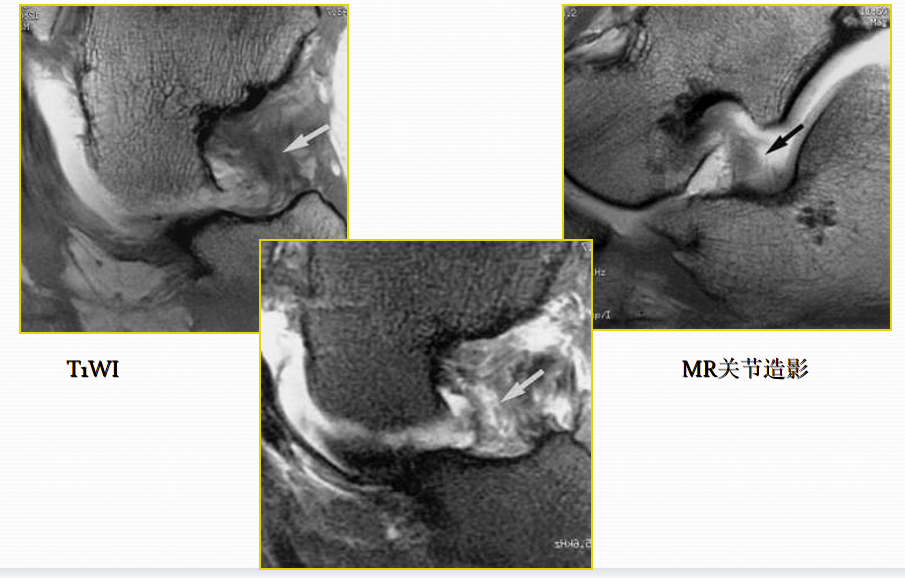

胫前、胫后肌腱撕裂

病因病理机制:

• 好发于中年人,胫骨前肌腱多见于登山运动员。

• 类风湿性关节炎、有副舟骨患者好发。

• 足踝运动障碍、疼痛。

• 胫骨后肌腱是维持足弓的重要力量,撕裂后易出现扁足。

MR表现:

• 胫骨前肌腱较少发生撕裂,一旦发生,多为全肌腱损伤

• 胫骨后肌腱出现横截撕裂或纵行撕裂

• 肌腱增粗,原本椭圆形的肌腱横断面变成圆形

• 可为横向或纵向撕裂;完全或部分撕裂

• 相应的腱鞘积液和鞘膜增厚

• 邻近关节见骨关节炎表现